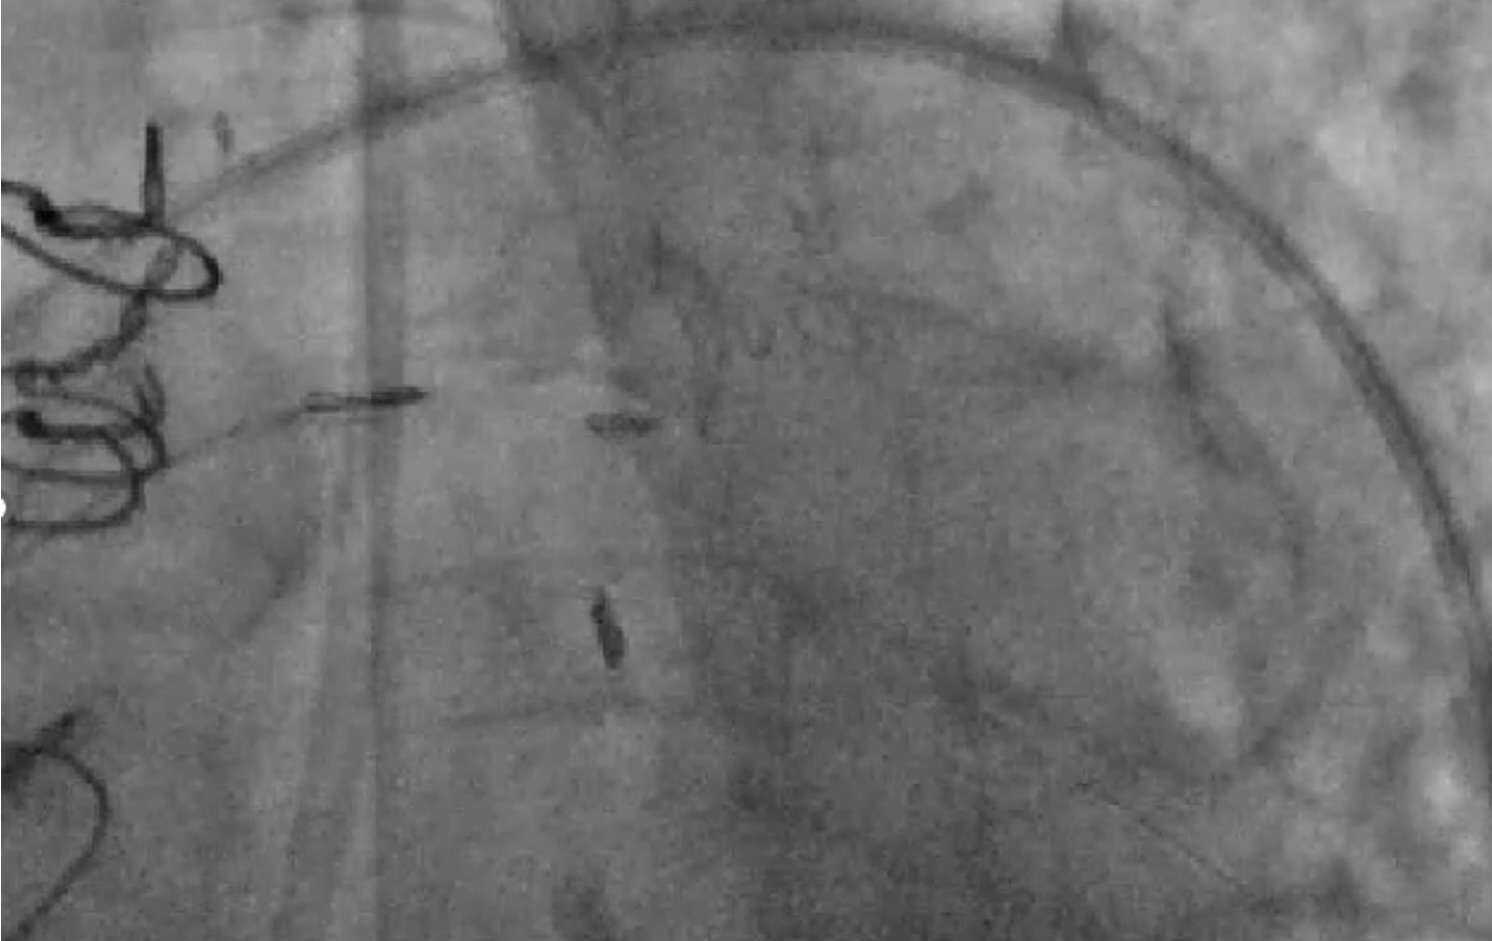

After shared decision-making, high-risk PCI was pursued. We used 7F equipment and an AL 0.75 guide. Angiography confirmed a severely calcified mid and ostial SVG lesion. A workhorse wire crossed the lesion, but neither microcatheter nor balloon could be advanced. These lesion characteristics even made Embolic protection devices (EPDs) infeasible and hence were not used. Laser Atherectomy was avoided due to heavy calcification, and Intravascular lithotripsy (IVL) was not feasible due to its large profile. Rotational atherectomy was pursued as a last resort. A microcatheter was deeply positioned, and a Rota floppy wire was advanced using a primary wiring technique. We then performed rotational atherectomy in the SVG graft with a 1.25 mm burr at 150,000 rpm. No perforation or vessel damage was seen. Subsequently sequential balloon angioplasty and stenting with 2.75 x 38 and 2.75 x26 mm stents were placed from distal graft body to ostium with significantly improved blood flow in the graft. Bailout strategies, including vascular plugs, coils, covered stents, and vasodilators, were prepared, alongside plans for prolonged DAPT.